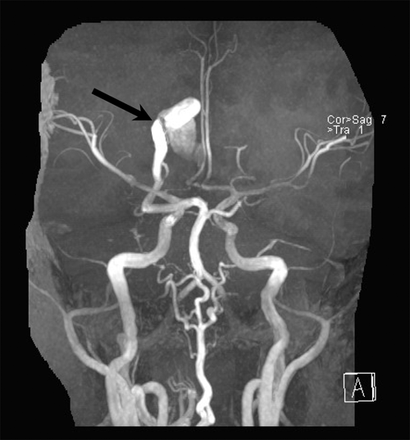

图2

磁共振血管造影

三维飞行时间磁共振血管造影显示动静脉瘘(箭头所指)之间的异常扩张盖伦的右大脑后动脉和静脉。